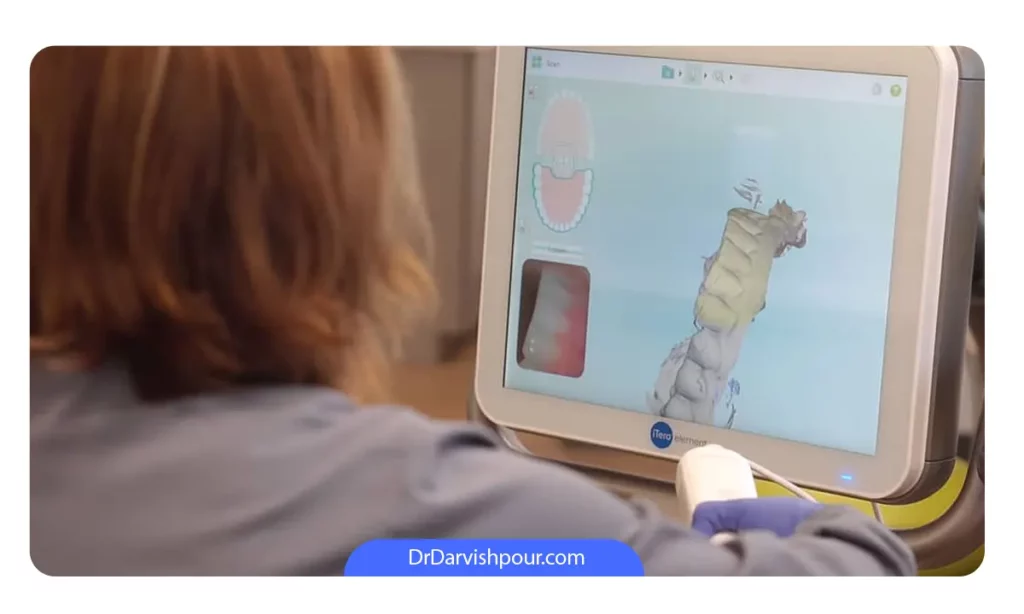

اگر شما جزو آن دسته از افرادی هستید که با شنیدن اسم خمیر قالب گیری ارتودنسی حالتان بد می شود، خبر خوبی برایتان داریم. امروزه تکنولوژی اسکن دیجیتال ارتودنسی تمام این مشکلات را حل کرده است. در این روش دیگر خبری از خمیرهای چسبناک، سینی های بزرگ و حس خفگی نیست. به جای آن، متخصص از یک دستگاه کوچک به نام اسکنر داخل دهانی استفاده می کند که شبیه به یک عصای نوری ظریف است.

نحوه قالبگیری دیجیتال به چه صورت است؟

دکتر این اسکنر را به آرامی در دهان شما حرکت می دهد و دستگاه در هر ثانیه هزاران عکس از دندان های شما می گیرد. این عکس ها بلافاصله در نرم افزار پردازش شده و یک مدل سه بعدی کاملاً دقیق و رنگی از دندان های شما روی مانیتور ظاهر می شود.

- همچنین دقت این روش بسیار بالاتر از روش سنتی است و احتمال خطا در ساخت دستگاه های ارتودنسی را به حداقل می رساند. این تکنولوژی به خصوص برای ساخت الاینرهای شفاف یا همان ارتودنسی نامرئی حیاتی است.